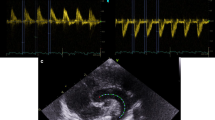

Pregnancies were divided into three groups: Intrauterine Growth Restricted (IUGR), Hypertensive, and Normal. Each group’s mean fetal cardiac time intervals (P, PR, QRS and RR) derived by magnetocardiography were calculated using an analysis of covariance model’s regression-adjusted estimates for a gestational age of 35 weeks.

We reviewed 141 recordings from 21 IUGR, 46 Hypertensive and 74 Normal patients. The IUGR, Hypertensive and Normal groups, respectively, had adjusted mean intervals in milliseconds of 66.4, 66.8 and 76.2 for P (P=0.001), 95.9, 101.6 and 109.6 for PR (P=0.002), 77.2, 78.7 and 78.7 for QRS (P=0.81) and 429.8, 429.2 and 428.5 for RR (P=0.97).

P and PR intervals are abbreviated in normotrophic fetuses exposed to maternal hypertension, suggesting shortened atrioventricular conduction times.